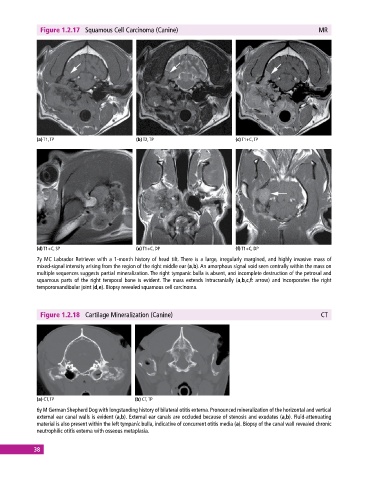

Figure 1.2.17 Squamous Cell Carcinoma (Canine) MR

(a) T1, TP (b) T2, TP (c) T1+C, TP

(d) T1+C, SP (e) T1+C, DP (f) T1+C, DP

7y MC Labrador Retriever with a 1‐month history of head tilt. There is a large, irregularly margined, and highly invasive mass of

mixed‐signal intensity arising from the region of the right middle ear (a,b). An amorphous signal void seen centrally within the mass on

multiple sequences suggests partial mineralization. The right tympanic bulla is absent, and incomplete destruction of the petrosal and

squamous parts of the right temporal bone is evident. The mass extends intracranially (a,b,c,f: arrow) and incorporates the right

temporomandibular joint (d,e). Biopsy revealed squamous cell carcinoma.

Figure 1.2.18 Cartilage Mineralization (Canine) CT

(a) CT, TP (b) CT, TP

6y M German Shepherd Dog with longstanding history of bilateral otitis externa. Pronounced mineralization of the horizontal and vertical

external ear canal walls is evident (a,b). External ear canals are occluded because of stenosis and exudates (a,b). Fluid‐attenuating

material is also present within the left tympanic bulla, indicative of concurrent otitis media (a). Biopsy of the canal wall revealed chronic

neutrophilic otitis externa with osseous metaplasia.